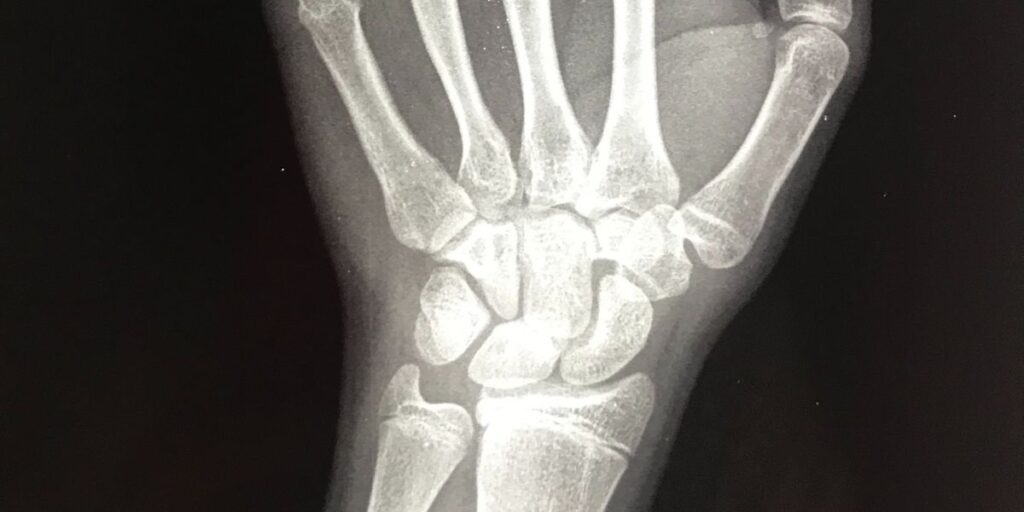

L’RX Polso, conosciuto anche come radiografia del polso, è un esame diagnostico che sfrutta i raggi X per produrre immagini dettagliate dell’area interessata. Presso il Poliambulatorio S-Medical Group di Sora, questo esame viene effettuato da tecnici radiologi altamente qualificati, utilizzando apparecchiature di ultima generazione che garantiscono immagini precise e di alta qualità. L’esame consente di individuare con esattezza eventuali anomalie ossee e articolari.

Attraverso l’RX Polso, è possibile ottenere una visualizzazione accurata delle ossa, delle articolazioni e delle altre strutture presenti nell’area del polso. Le immagini prodotte evidenziano eventuali fratture, deformazioni o segni di degenerazione articolare, rendendo l’esame essenziale per una diagnosi completa e dettagliata. Al Poliambulatorio S-Medical Group di Sora, le immagini radiografiche vengono analizzate attentamente dai medici per identificare con chiarezza la natura del problema.